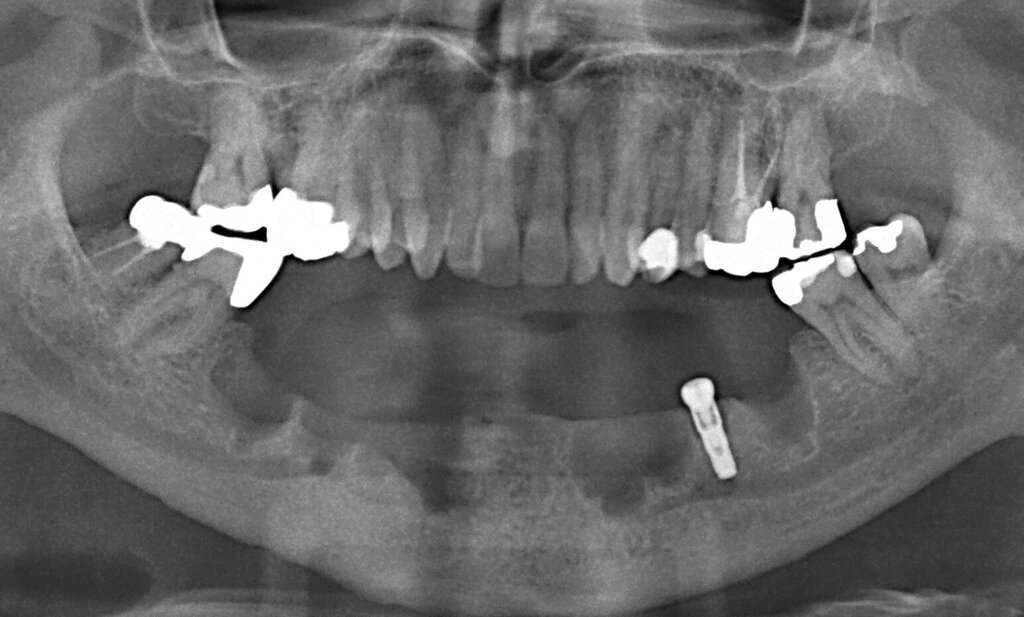

Ursprünglich waren bei dieser Patientin nach einem Frontzahntrauma vier Implantat-gestützte Kronen geplant. Nach dem frühen Verlust des Implantats in regio 21 während der Einheilzeit wurde dann eine auf drei Implantaten abgestützte Brücke eingegliedert. Das bestehende vertikale und horizontale Weichgewebsdefizit wurde bei der verschraubten Implantatbrücke durch aufgebrannte rosafarbene Keramik kaschiert (Abb. 3a). Funktionell war die Brückenversorgung über viele Jahre erfolgreich und zeigte keinerlei Lockerungsgrad. Trotz guter Mundhygiene war in Kontrollsitzungen ein kontinuierlicher Knochenabbau an allen Implantaten festzustellen (Abb. 3b). Zur Vermeidung eines weiteren Knochenverlusts fiel circa 15 Jahre nach der Erstversorgung die Entscheidung zur Explantation. Zu diesem Zeitpunkt war die Patientin 55 Jahre alt.

Nach dem Abschrauben der Suprastruktur (Abb. 3c und 3d) wurden alle Implantate unter Lokalanästhesie mit einem passenden Trepanbohrer umbohrt und ohne Lappenbildung entfernt. Die temporäre Lückenversorgung erfolgte mit einer herausnehmbaren Prothese, die über Gussklammern am Restgebiss abgestützt war.

Da sechs Monate nach der Explantation keine nennenswerte knöcherne Regeneration festzustellen war, wurde eine zweizeitige Implantation nach Knochenaugmentation mithilfe dünner Knochenscheiben aus dem Kieferwinkel geplant. Die Entnahme erfolgte mit oszillierenden Instrumenten (Piezosurgery). Der Knochenblock wurde in dünne Scheiben geschnitten und mit Osteosyntheseschrauben am Alveolarfortsatz fixiert (Abb. 3e). Darüber wurden die Weichgewebe dicht vernäht. Weitere fünf Monate später erfolgte die Schraubenentfernung und die Implantation von zwei Bone-Level-Implantaten in regio 12 und 22 mit geschlossener Einheilung (Abb. 3f und 3g). Bei der Implantatfreilegung weitere sechs Monate später wurden die Weichgewebsdefizite im Brückengliedbereich durch ein kombiniertes Bindegewebs-/Schleimhauttransplantat aufgefüllt und gleichzeitig die keratinisierte periimplantäre Gingiva und Alveloarmukosa verbreitert (Abb. 3h und 3i). Die prothetische Versorgung erfolgte erst weitere drei Monate später, nach dem Konsolidieren der Weichgewebe. Die umfangreichen Augmentationsmaßnahmen konnten das transversale Weichgewebsdefizit vollständig kompensieren, während das verbleibende vertikale Defizit zu zervikal etwas längeren Kronen und Brückengliedern führte. Aufgrund der guten Abdeckung durch die Oberlippe kann das ästhetische Ergebnis als zufriedenstellend bewertet werden (Abb. 3j bis 3l).